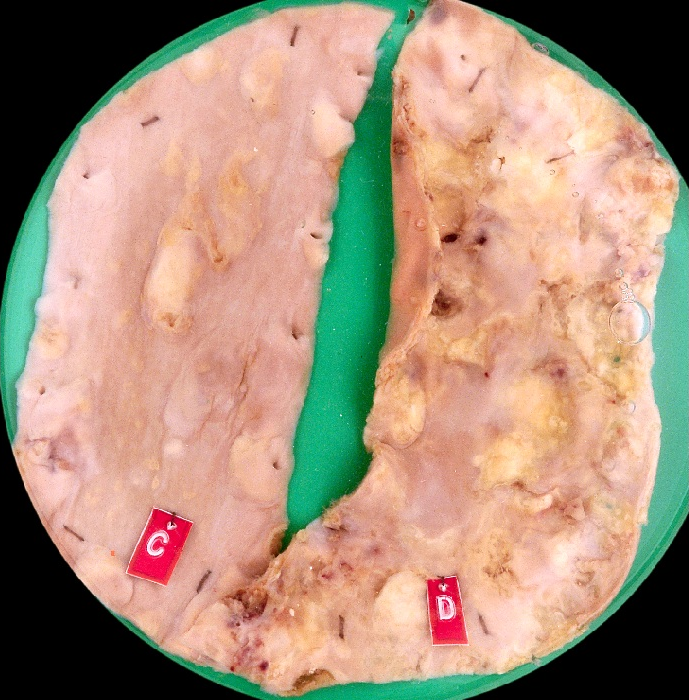

Changes can occur at the macroscopic or gross level, which means you can see the changes with your eyes or they can happen at the microscopic level, which means you need a light microscope or an electron microscope to see the changes. Histopathology is the study of the tissues to identify changes at the cellular or microscopic level.

We saw from the previous example that pathology is also a medical specialty (you need to be a doctor). There are different specialties within Pathology. Anatomic Pathologists look at tissues and organs to determine disease based on changes in the appearance of cells, tissues and organs, both grossly and microscopically and often specialize in a particular organ system. Forensic Pathologists look specifically at why a person has died and so examine the whole body as well as specific tissues and organs and also order toxicological tests to look for foreign substances in the body that may have contributed to the death. Neuropathologists specialize in the nervous system and muscle pathology. Hematopathologists specialize in changes to the blood cells and has Transfusion medicine as a subspecialty. Medical Microbiologists isolate, grow and identify micro-organisms that cause disease, along with which treatments may be effective against them. They work with Infectious Disease specialists to identify and treat communicable diseases and prevent their spread in the community. Medical Biochemists and Clinical Chemists look after the laboratory testing of chemical substances in the body, either produced by the body or ingested; determining what is the best method to use, what the limitations of the tests are, and what are the normal ranges of values for a given test.